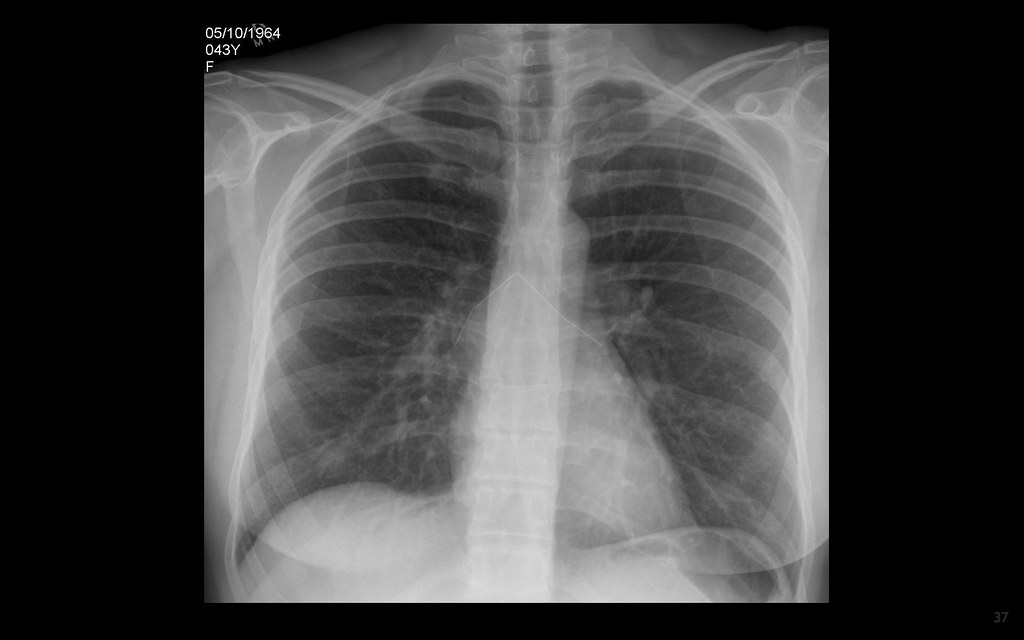

Also started with shortness of breath, sweating and feeling or being sick; Web summary chest pain that comes and goes may be related to the heart, the muscles, the digestive system, or psychological factors. In certain cases, the pain travels up the neck and into the jaw and then spreads to the back or down one or both arms.

In certain cases, the pain travels up the neck and into the jaw and then spreads to the back or down one or both arms. Chest pain appears in many forms, ranging from a sharp stab to a dull ache. You can experience different types of chest pain.

Common descriptors of visceral pain are dull, deep, pressure, and squeezing. A workup must focus on ruling out serious pathology before a clinician considers more benign causes. Possible causes include gastrointestinal problems, panic attacks,.

Pain in the jaw, neck, or back lightheadedness or weakness pain in the arms or shoulders shortness of. Web you have sudden chest pain that: Heart attack chest pain is one of the main symptoms of a heart attack.